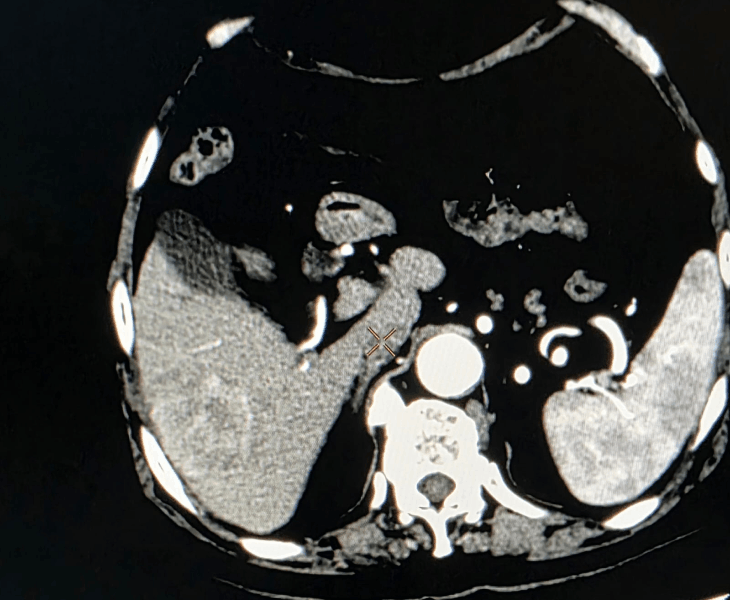

Post treatment

- Chemoembolization (TACE): delivers chemotherapy directly into the tumour’s blood supply, followed by embolic particles to block the vessels and cut off nutrition to the cancer.

Post treatment (TACE) procedure

Chemoembolization of liver cancer before

After treatment